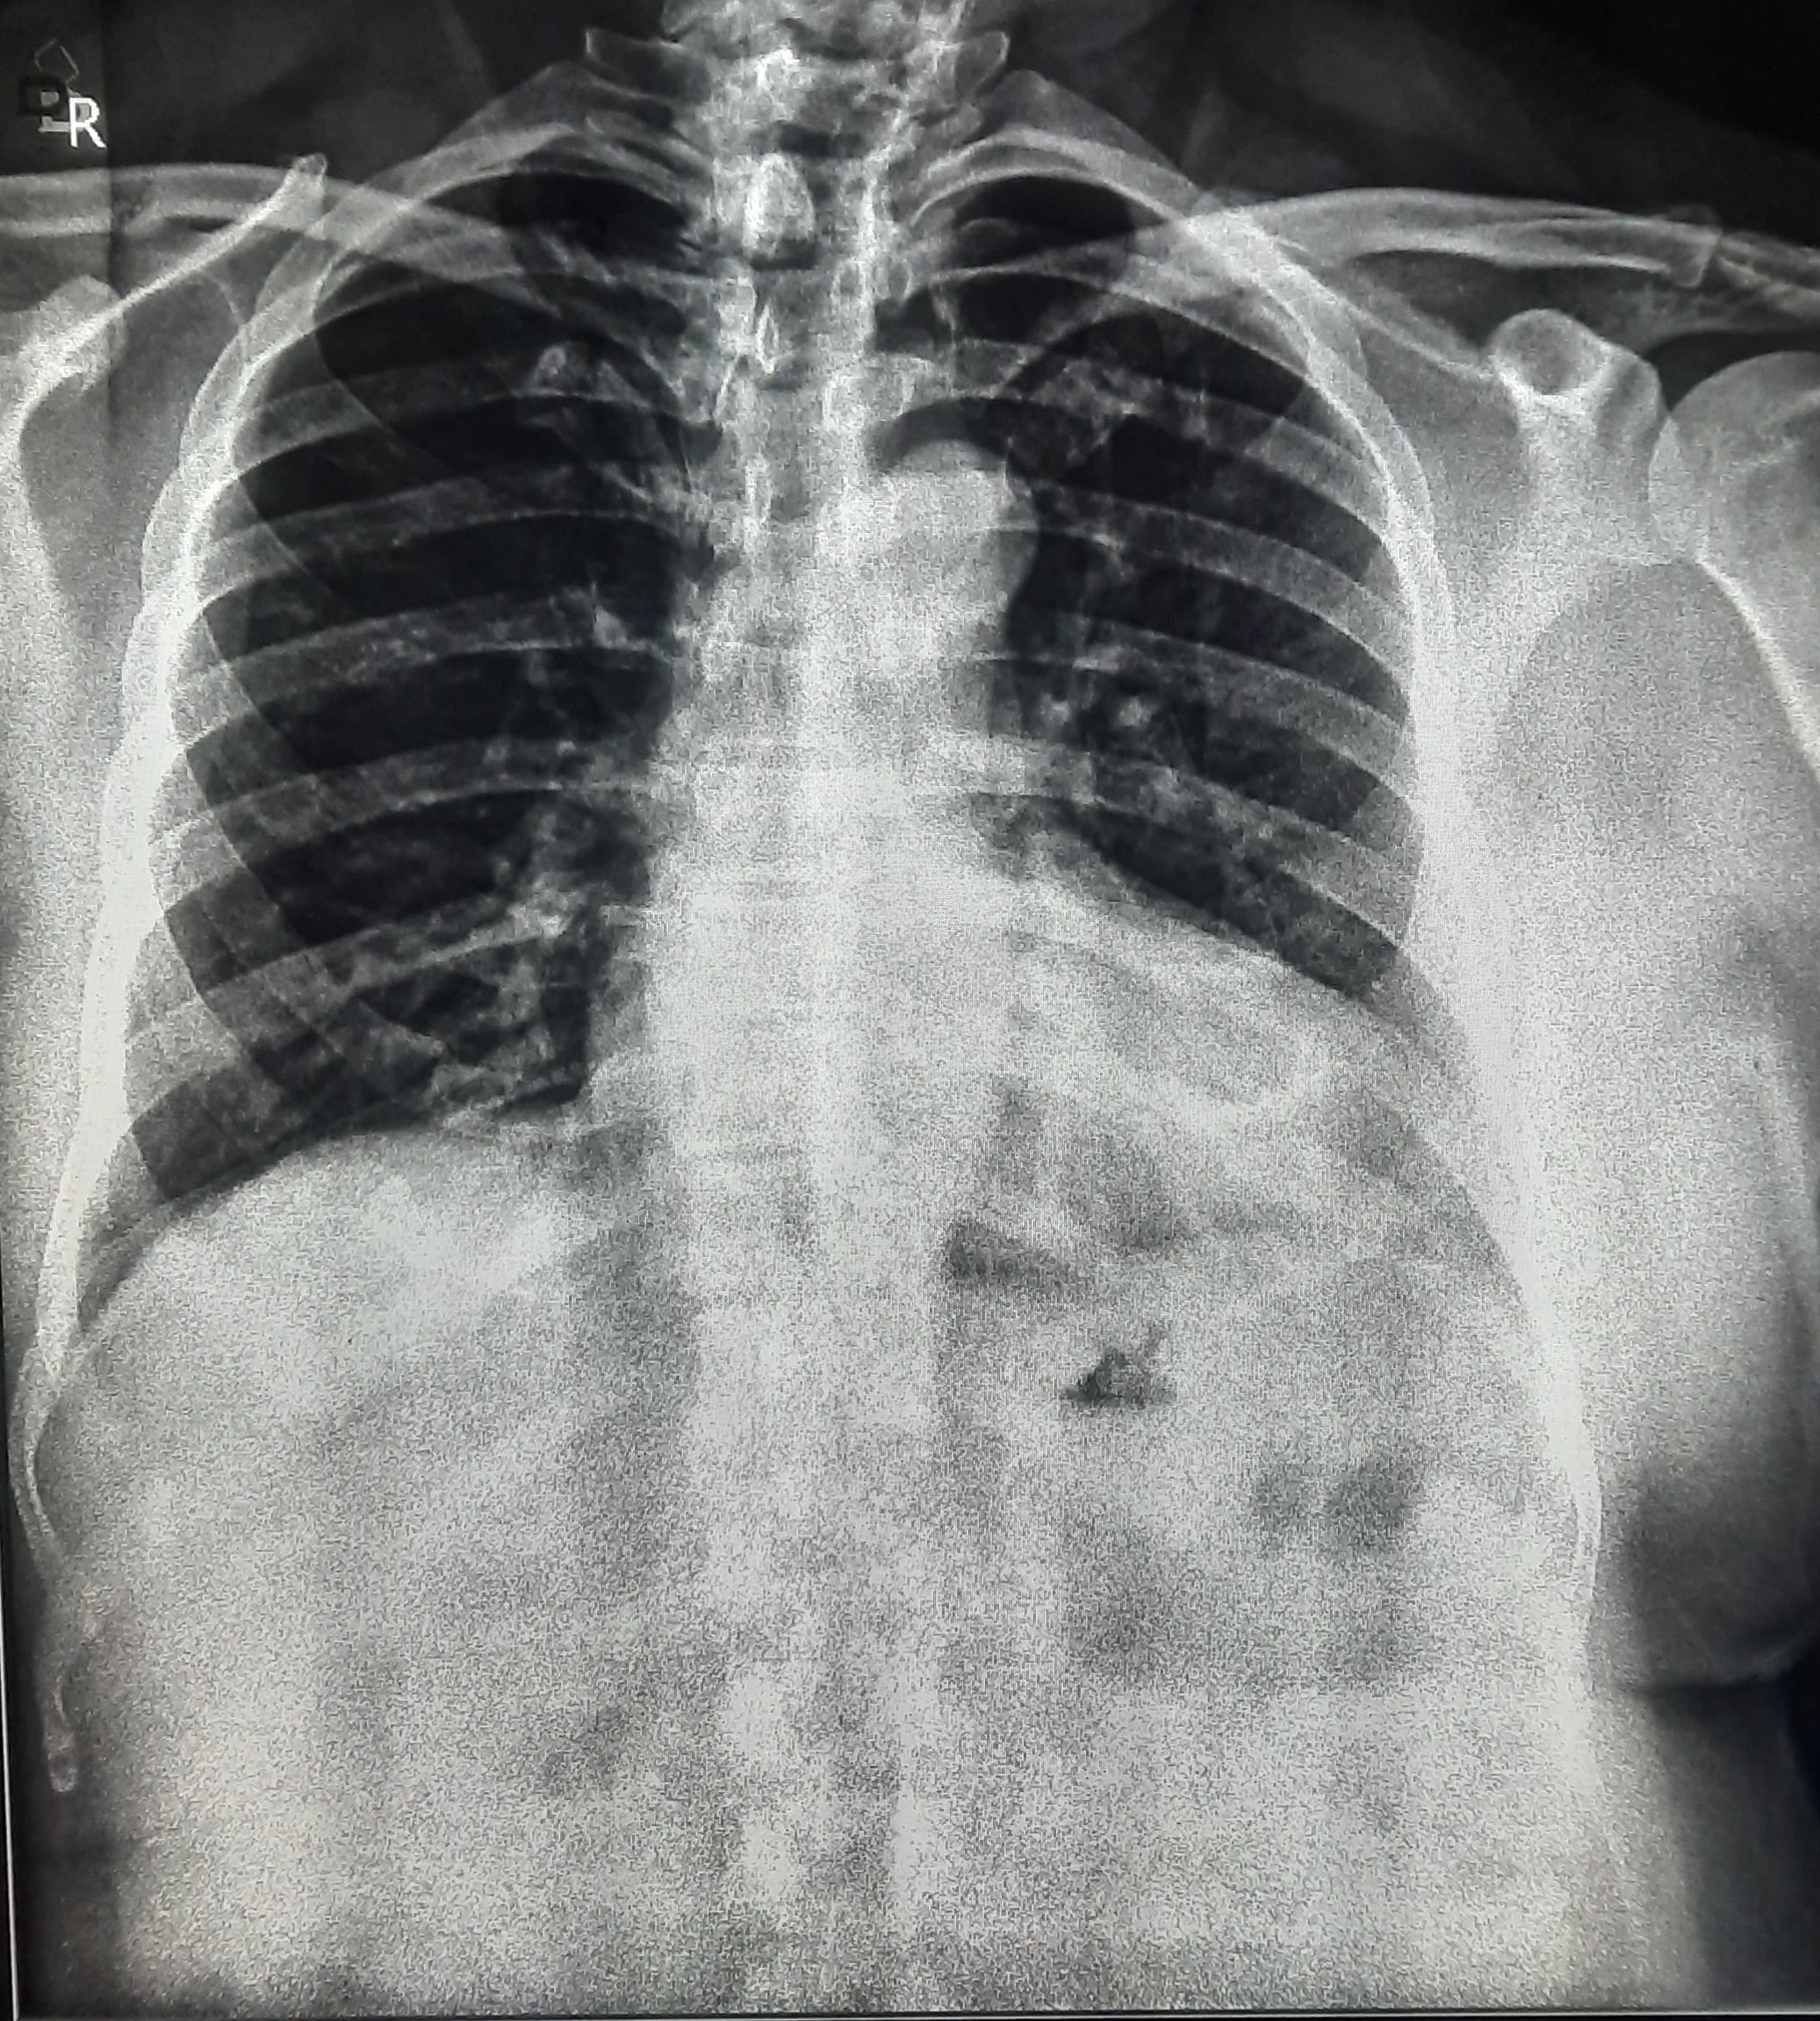

| 51 | IGGMC, Nagpur, Nagpur | P2 | 29-4421 | Santosh Neware | Consent taken on Paper | 40 Yrs. |

Provisional Diag : Pulmonary Tuberculosis

Final Diag : Pulmonary tuberculosis (Microbiologically Confirmed PTB) |

TB Case (Confirmed) | Right Upper & mid zone fibro cavitary lesion present, upward pull of right hemidiaphragm, tracheal pull right sided | Abnormality visible on x-ray |